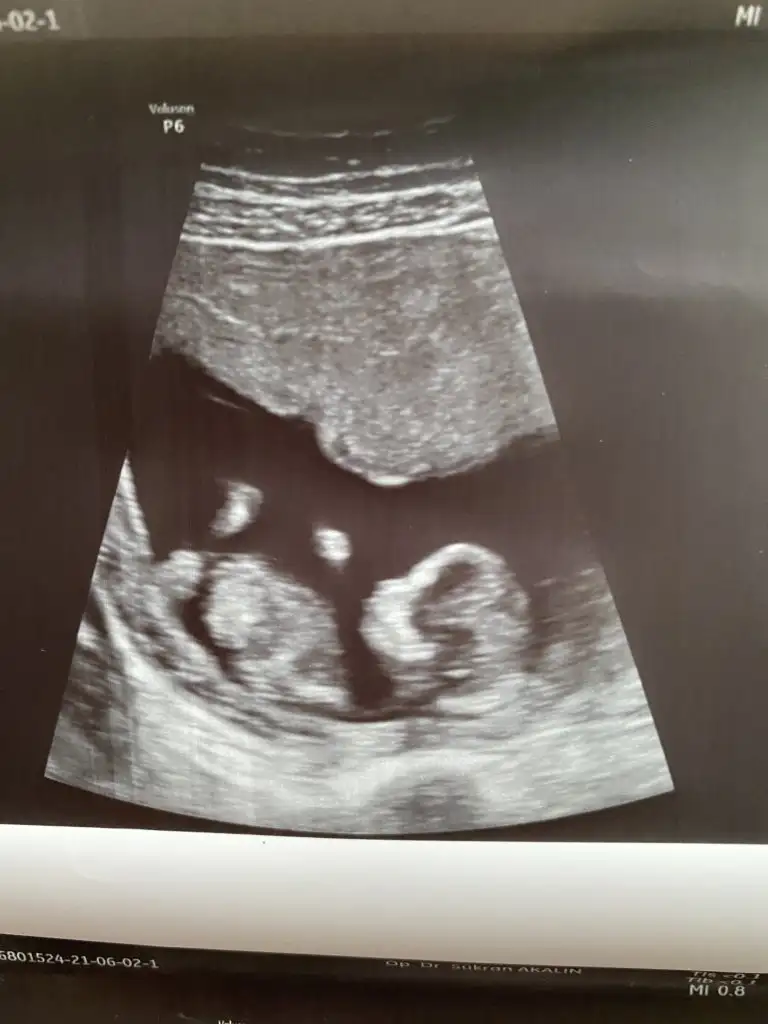

Ben bugün gene kontroldeydim Ikra meyra her seferin farklı tahminde bulunuyor ama bugün met ve emin söyledi. Bakalım sen ne diyeceksin? Bemce poposu dönük ama öyle bişey demedi.

Eklentiler

• 75A4491F-6DB9-4A8B-8E02-02864430ECE0.webp

13 KB · Görüntüleme: 79

• 4823C446-5F34-47E2-917C-5CA695CA87DF.webp

24,3 KB · Görüntüleme: 67

• E969A068-7C17-45EB-ACF3-EBD5B5F8B5D2.webp

23,8 KB · Görüntüleme: 76

Kız gibi sanki daha önceki karanlık USG emin olmamıştım